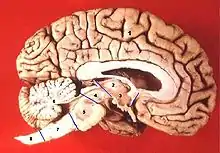

Akinetic mutism can occur in the frontal region of the brain and occurs because of bilateral frontal lobe damage. Akinetic mutism as a result of frontal lobe damage is clinically characterized as hyperpathic.[5] It occurs in patients with bilateral circulatory disturbances in the supply area of the anterior cerebral artery.[2]

Mesencephalic akinetic mutism

Akinetic mutism can also occur as a result of damage to the mesencephalic region of the brain. Mesencephalic akinetic mutism is clinically categorized as somnolent or apathetic akinetic mutism.[5] It is characterized by vertical gaze palsy and ophthalmoplegia. This state of akinetic mutism varies in intensity, but it is distinguished by drowsiness, lack of motivation, hyper-somnolence, and reduction in spontaneous verbal and motor actions.[2][5]